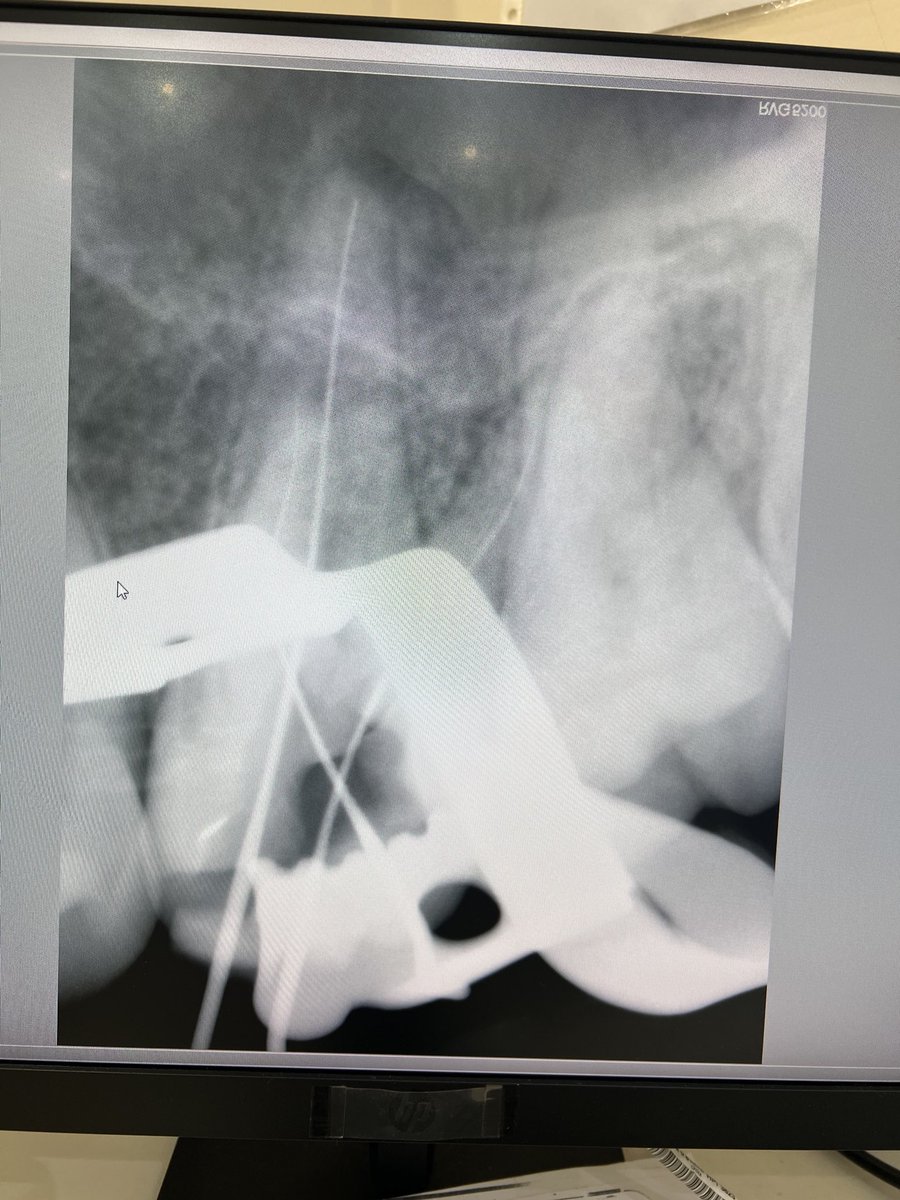

Today’s case✨: Replacement of missing #26 was accomplished using a zirconia fixed bridge (Shade B2). Tooth #27, previously endodontically treated, was reinforced with a fiber post and core build-up. Ensuring functional stability and optimal esthetics.